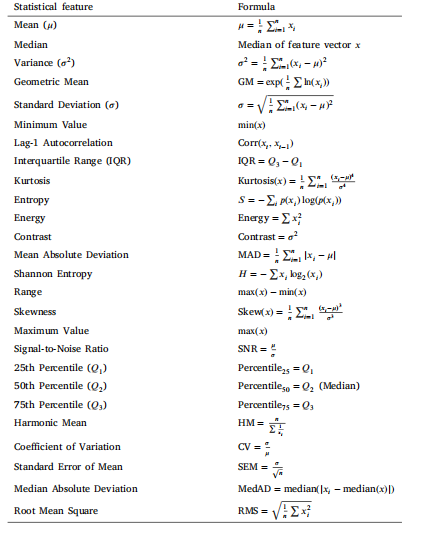

近年来,人工智能(AI)和深度学习(DL)彻底改变了对预测准确性要求较高的领域,尤其在医疗健康、刑事司法等高风险应用中表现突出(Aamir等人,2021)。在医疗健康领域,深度学习模型显著提高了多种成像模态下的诊断准确性,包括磁共振成像(MRI)、胸部X光片、组织病理学和超声检查(Qayyum等人,2024;Ullah等人,2023)。尽管这些模型取得了成功,但它们因缺乏透明度和可解释性而受到批评,这在医疗健康等关键领域引发了信任和伦理方面的担忧(Rudin,2019;Poon和Sung,2021)。 为应对这些挑战,可解释人工智能(XAI)和可解释性人工智能(IAI)应运而生(Ullah等人,2024a)。XAI技术对深度学习模型的决策逻辑进行解释,在不牺牲准确性的前提下提高透明度和信任度。事后XAI方法,如特征重要性排序(Wojtas和Chen,2020)、显著图(Gomez等人,2022)和基于梯度的可视化(Selvaraju等人,2017),旨在揭示黑箱模型的内部机制。相比之下,IAI开发具有内在透明度的模型,如决策树或基于规则的系统,以人类可理解的形式呈现决策过程(Reyes等人,2020;De Falco等人,2023)。 然而,一些关键局限性仍然存在。尽管从卷积层提取的深度特征在分类任务中有效,但这些特征较为抽象,缺乏专家可理解的语义互操作性,使得人们难以理解特定特征如何影响决策。此外,大多数可视化方法(如显著图)仅突出与预测相关的一般输入区域,无法提供详细的特征级解释。基于规则的方法往往缺乏与视觉解释的整合,导致见解碎片化。这种脱节在医疗健康领域尤其成问题,因为透明且精确的解释对于信任和决策至关重要。 为解决这些问题,本研究提出了统计、视觉和基于规则的可解释框架(SVIS-RULEX)。这个新框架整合了统计、视觉和基于规则的解释,以说明基于深度学习的模型在处理医学图像时如何做出决策。与传统方法不同,该框架将深度特征转化为可解释的统计属性,实现可追踪和可量化的预测。此外,还引入了一种名为SFMOV的新方法。SFMOV通过将统计量(如均值、偏度、熵)叠加到特征图上来增强可视化效果,提供局部化和特定于特征的见解。通过融合统计、视觉和基于规则的解释,这种方法确保了更高的透明度和可解释性,这对医疗健康应用至关重要。 为验证其稳健性和通用性,SVIS-RULEX框架在来自Kaggle的五个不同医学影像数据集上进行了评估,涵盖胸部X光片、乳腺超声、脑部MRI、组织病理学和眼底图像。这种广泛的评估证明了该框架在各种成像模态和疾病条件下的适应性和有效性。 本研究的主要贡献总结如下: 1. 一种双路径方法,整合视觉和基于规则的解释,以增强可解释性同时保持分类性能。 2. 使用定制的MobileNetv2模型提取深度特征,捕捉来自不同医学成像模态的高维表示。 3. 引入一种新颖的统计特征工程方法,从深度特征中生成26个人类可理解的属性(如均值、方差、偏度、熵),以提高可解释性。 4. 开发新颖的ZFMIS策略用于特征排序和选择,确保特征集紧凑且信息丰富。 5. 使用决策树(DT)和RuleFit进行基于规则的解释,为模型的决策过程提供人类可理解的见解。 6. 提出新颖的SFMOV技术,可视化卷积特征的统计叠加(均值、偏度、熵),并通过密集层属性加权,以实现更深层次的可解释性。 7. 与放射科医生一起对SFMOV可视化进行临床验证,确认其诊断相关性和实际意义。 论文的其余部分结构如下:第2节回顾相关工作。第3节详细介绍所提出的方法。第4节展示并讨论结果,第5节总结全文。

This work integrates rule-based modeling and visualizations withstatistical feature engineering and DL-based feature extraction to produce human-understandable explanations. This method bridges thegap between interpretable techniques’ transparency and black-box DLmodels’ predictive power. Fig. 1 shows an overview of the proposedmethod. First, some existing techniques are used in preprocessing, likedata augmentations, image resizing, and region of interest cropping.The resultant dataset is then fed into the custom MobileNetv2 DL modelfor feature extraction to capture complex visual patterns and get morediscriminative and informative deep features, which are crucial foraccurate classification. These extracted features are then used for statistical transformation to compute interpretable, summary-level insights.Next, a novel ZFMIS technique ranks and filters features based on theirinterpretive value. The filtered and selected features are then used totrain the decision tree and RuleFit interpretable rule-based models. Finally, Grad-CAM-inspired heatmaps (SFMOV) are generated to visualizethe most important statistical features and highlight spatial regions ofthe images that contribute significantly to the model’s decision-makingprocess. Visual overlays enhance statistical interpretation by illustrating how specific patterns affect categorization judgments, providingstakeholders with an intuitive understanding of the prediction model’sbehavior, a model-agnostic visual explanation technique.The pseudocode of the proposed methodology is presented in Algorithm 1. Each step is discussed in detail in the subsequent sections

本研究将基于规则的建模、可视化技术与统计特征工程及基于深度学习(DL)的特征提取相结合,生成人类可理解的解释。该方法填补了可解释技术的透明度与黑箱深度学习模型的预测能力之间的差距。图1展示了所提方法的整体框架:首先,采用一些现有技术进行预处理,如数据增强、图像 resize 和感兴趣区域裁剪;然后,将处理后的数据集输入定制的 MobileNetv2 深度学习模型进行特征提取,以捕捉复杂的视觉模式,获得更具判别性和信息量的深度特征——这些特征对准确分类至关重要;接着,利用这些提取的特征进行统计转换,计算可解释的、汇总级别的洞察;之后,一种新颖的 ZFMIS 技术根据特征的解释价值对其进行排序和筛选;再将经过筛选和选择的特征用于训练决策树和 RuleFit 这两种可解释的基于规则的模型;最后,生成受 Grad-CAM 启发的热图(SFMOV),以可视化最重要的统计特征,并突出对模型决策过程有显著影响的图像空间区域。视觉叠加通过说明特定模式如何影响分类判断,增强了统计解释的效果,为相关人员提供了对预测模型行为的直观理解,这是一种与模型无关的视觉解释技术。 所提方法的伪代码如算法1所示。后续章节将详细讨论每个步骤。

Table 1Statistical feature descriptions and formulas.

表1 统计特征描述及公式。